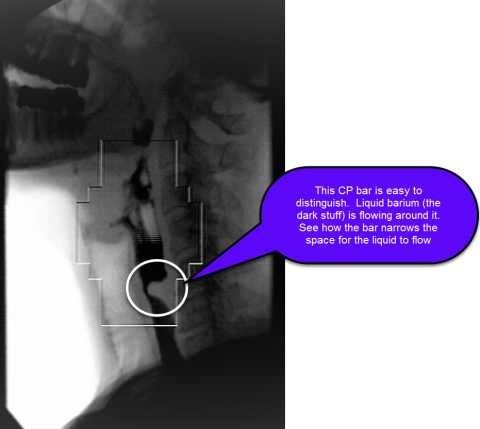

Diagnosis of the CP bar is made with fluoroscopic swallow study of the pharynx and proximal esophagus, typically in the lateral view. The bar appears as an indentation on the barium column at the posterior aspect of the esophagus between the C3 and C6 vertebral levels (see figure).